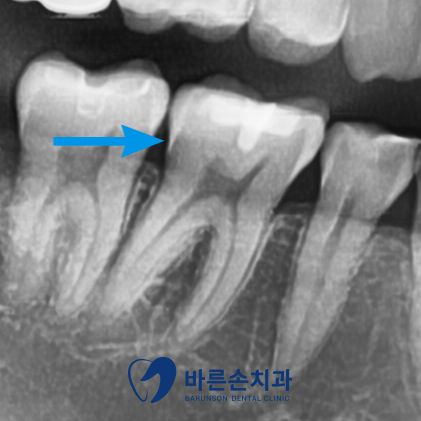

사진에서 보시면

■ 오른쪽 아래 첫번째 큰 어금니의 교합면 우식 -> 인레이